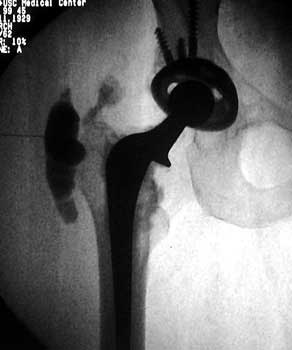

Normal arthrogram